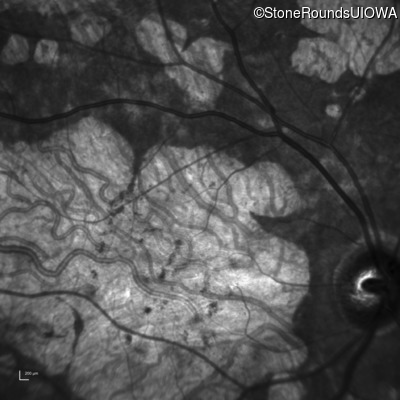

Infrared Fundus Photograph - Right - 20/200 +1 sc

Exemplar